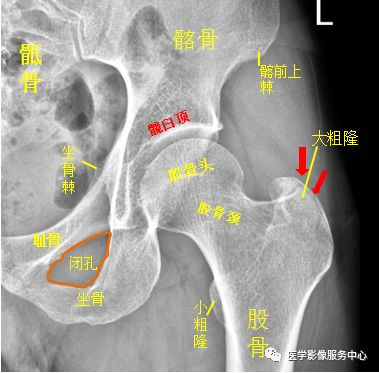

髋关节

图片

左侧股骨大粗隆处见不规则透亮线影,骨折处无明显分离、移位。左侧股骨大粗隆骨折。